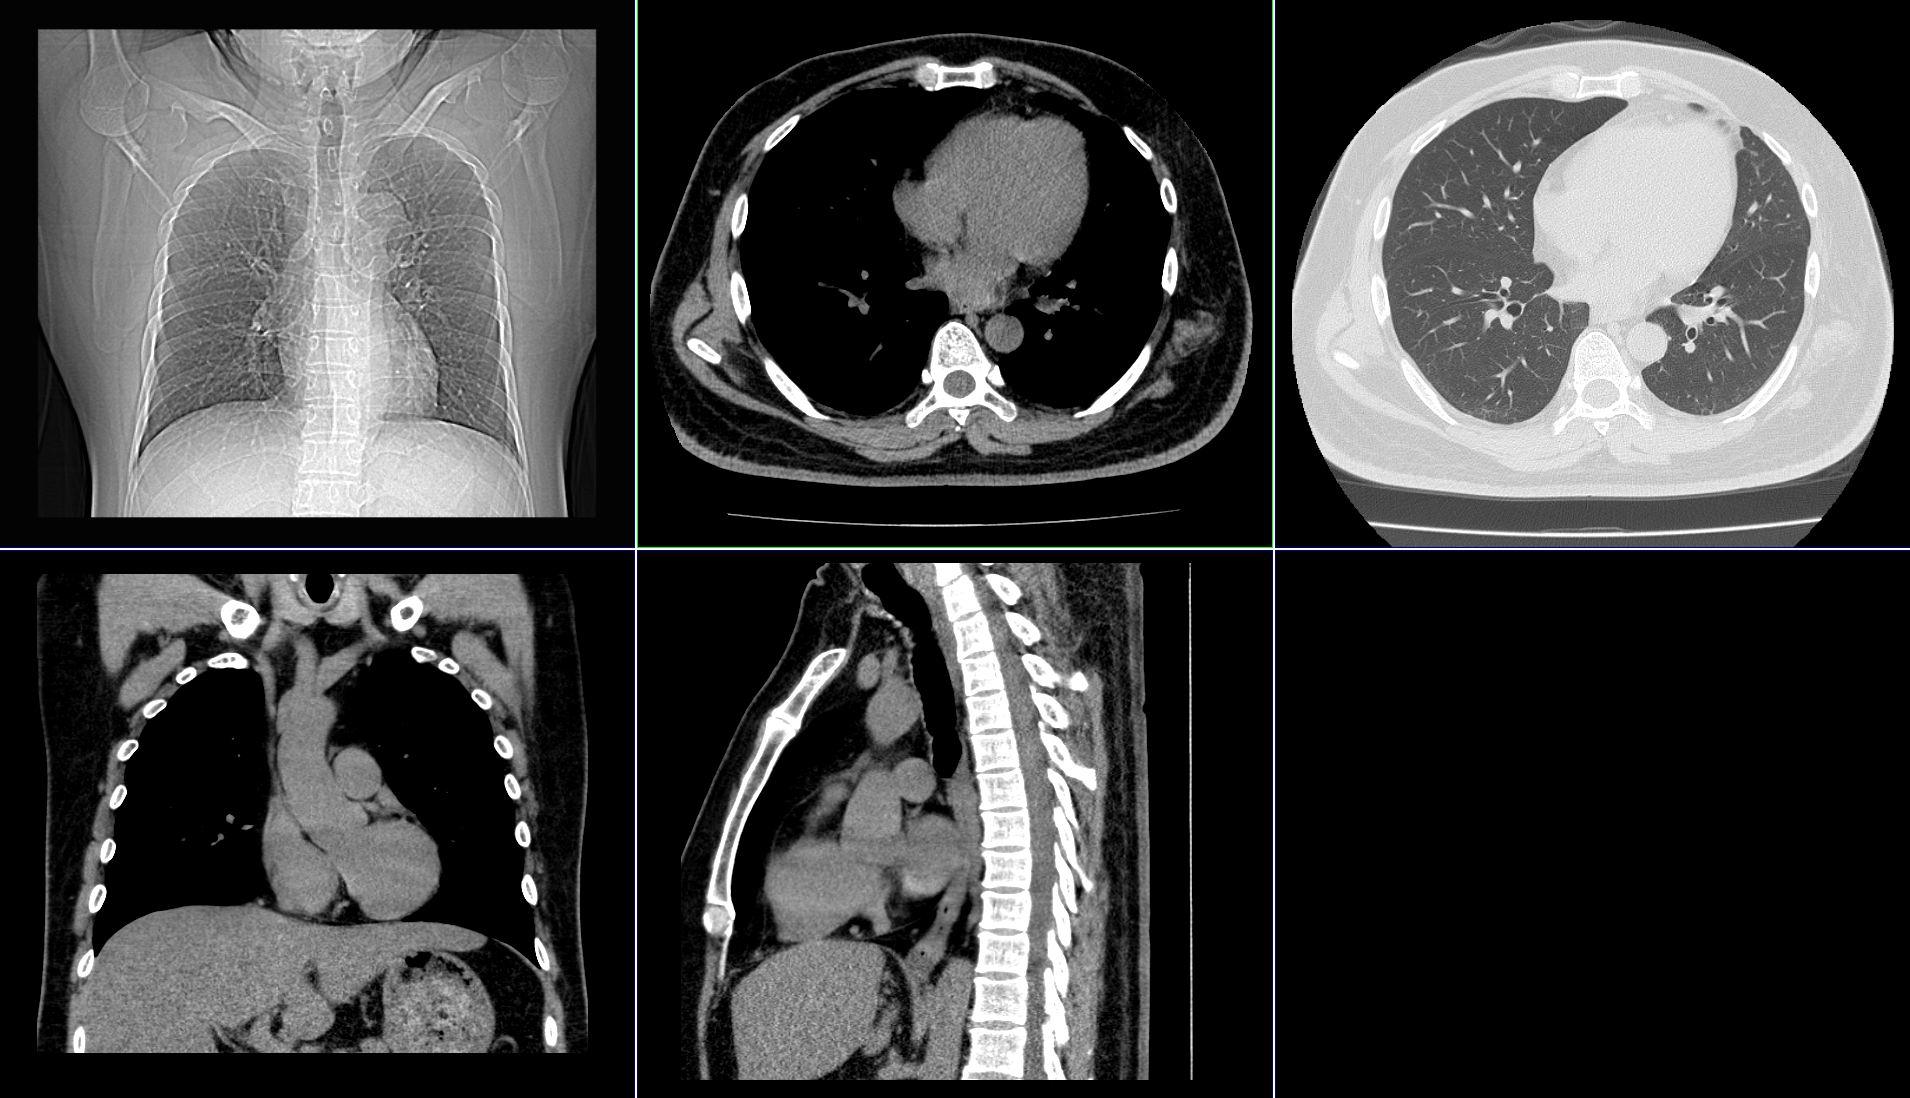

| 単純CT検査 | X線を使用して体の輪切りの写真を撮影します。

| 造影CT検査 |

造影剤を使用して撮影します。血管や病変部位など、より詳しい情報が得られます。 この情報をもとに、3D画像等の画像を作ることも可能です。 |